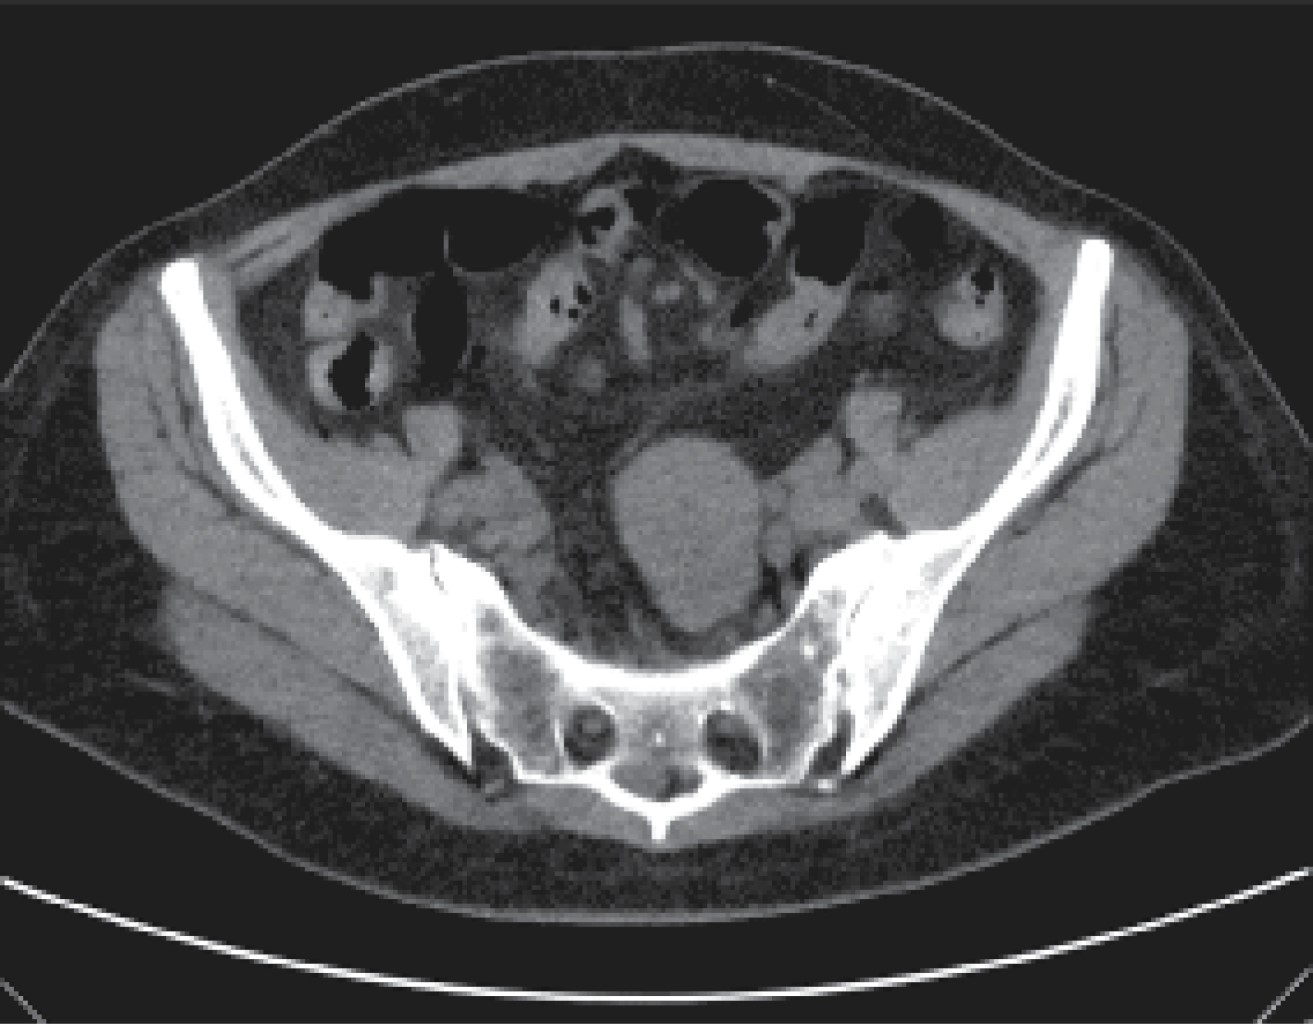

La tomografía axial computada (TAC) revela tumoración estenosante e infiltrante de las paredes del íleon con lumen estrecho y distensión de asas intestinales (Figuras 2 y 3).

Figura 3